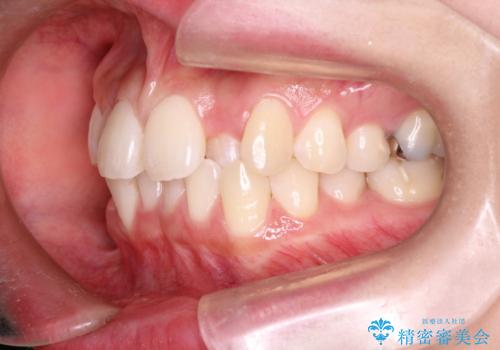

- 前歯の正中離開の改善を希望され来院された患者様です。

初診時の歯並びの状態としては、上下ともに前歯部の中等度のがたつきがあり、特に左上の前歯が1本内側に入り込んでしまっている状態でした。

また、2mm程度の正中離開がありました。

抜歯なし/インビザラインによるマウスピース矯正にて治療を行いました。

内側に入り込んでしまっている歯を出してくることに非常に時間がかかりましたが、一度歯を歯茎の方へ押し込みそして前へ出してくる2段階の治療を行いました。